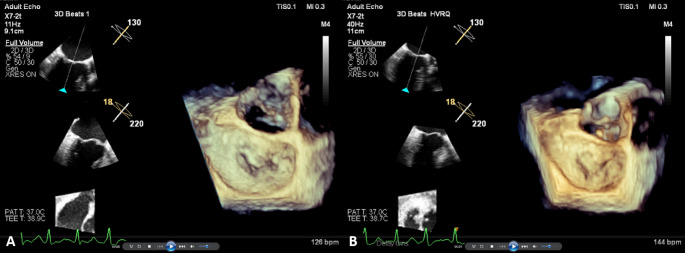

Meticulous understanding of the mechanisms underpinning mitral regurgitation in atrial fibrillation (AF) patients is crucial to optimize therapeutic strategies. The morphologic characteristics of mitral valves in atrial functional mitral regurgitation (FMR) patients with and without left ventricular (LV) dysfunction were evaluated by high volume rate (HVR) three-dimensional transesophageal echocardiography (3D-TEE). In our study, 68 of 265 AF patients who underwent 3D-TEE were selected, including 36 patients with AF, FMR, and preserved LV function (AFMR group) and 32 patients with AF, FMR, and LV dysfunction (VFMR group). In addition, 36 fever patients without heart disease were included in the control group. Group comparisons were performed by one-way analysis of variance for continuous variables. The left atrium (LA) was enlarged in the AFMR and VFMR groups compared with the control group. The mitral annulus (MA) in the AFMR group was enlarged and flattened compared with the control group and was smaller than in the VFMR group. The annulus area fraction was significantly diminished in the AFMR and VFMR groups, indicative of reduced MA contractility. The posterior mitral leaflet (PML) angle was smallest in the AFMR group and largest in the control group, whereas the distal anterior mitral leaflet angle did not significantly differ among the three groups. LA remodeling causes expansion of the MA and reduced MA contractility, disruption of the annular saddle shape, and atriogenic PML tethering. Comparison of atrial FMR patients with and without LV dysfunction indicates that atriogenic PML tethering is an important factor that aggravates FMR. HVR 3D-TEE improves the 3D temporal resolution greatly.